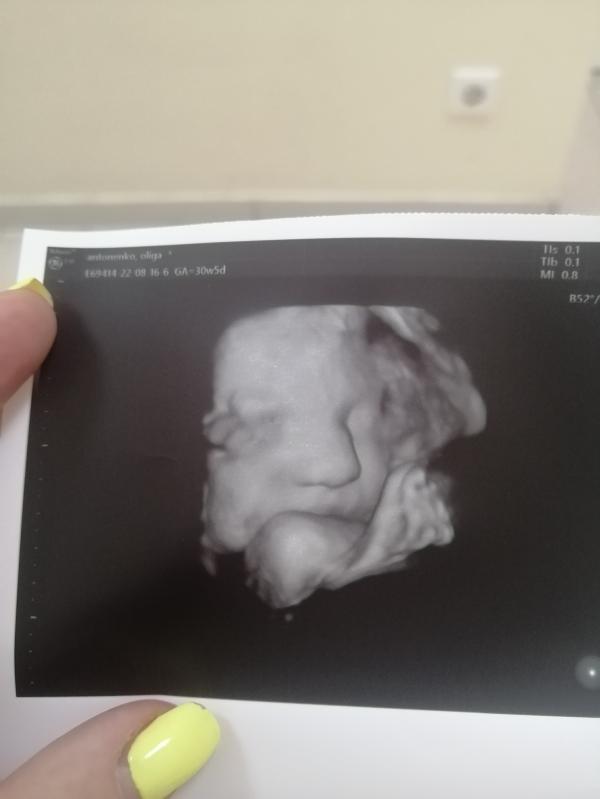

Моя карамелька! Сегодня ходили на 3й скрининг, не хотела фотографироваться, руками закрывала ротик. Вес сказали +-1550кг, сколько ваши детки весили на таком сроке? У нас все замечательно, все соответствует сроку, единственное врач сказала, что в плаценте есть перегородка и она мне её показала, спросила серьёзно ли это?! Она сказала, что не беспокойтесь на малыша она никак не влияет, просто она так сформировалась. Может было у кого так? Что то как то не по себе.